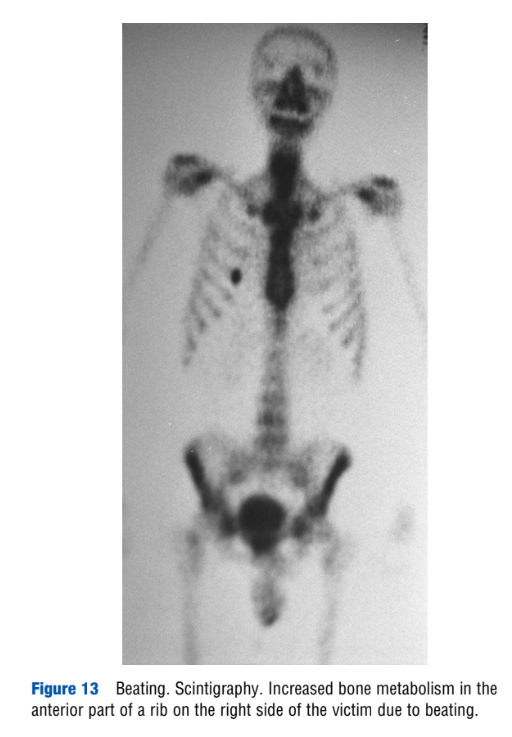

“Torture,” by H. Vogel. Encyclopedia of Forensic Sciences, second edition. 2013.